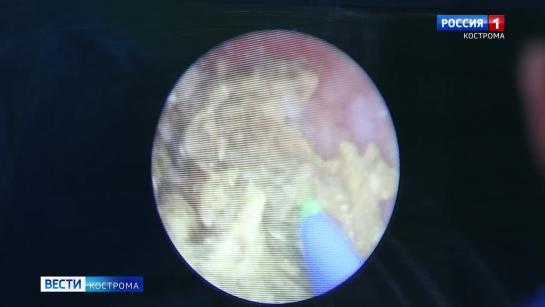

ТУР, тулиевая и гольмиевая энуклеация аденомы простаты 2,457 views 11 months ago 2 minutes, 44 seconds Uploaded by Медицинский центр «МИРТ» г. Кострома Related videos 1:53 1:13 1:15 1:51 5:29 2:20 1:25 3:12 2:43 4:14 1:55 1:34 1:11 2:18 4:32 2:54 6:35 5:57 1:45 1:15 1:18 10:00 1:13 2:02 6:05 4:05 7:49 4:30 62:00 0:40 1:16 5:08 0:55 2:20 2:40 1:31